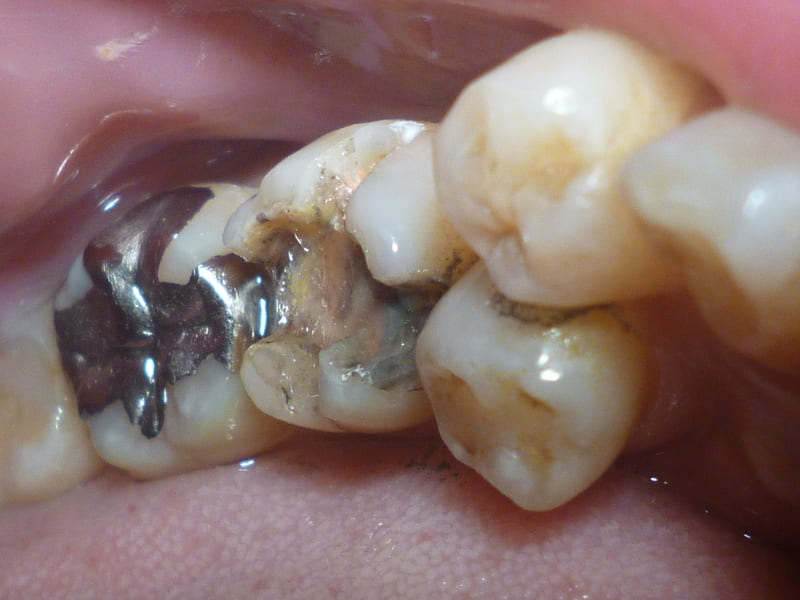

症例写真1:術前